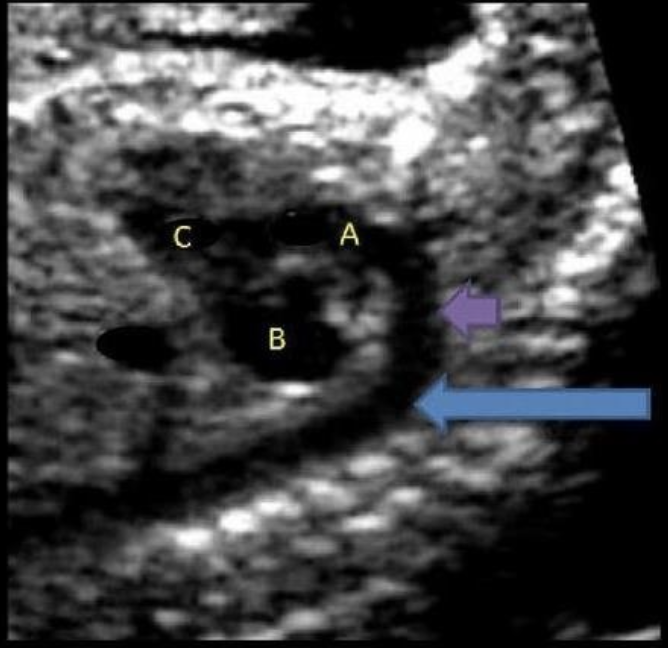

what is letter B

a) LVOT

b) RVOT

c) left ventricle

d) right ventricle

e) right atrium

what is letter E

a) left ventricle

b) LVOT

c) RVOT

d) right atrium

e) left atrium

letter C is what

a) left atrium

b) left ventricle

c) right atrium

the blue arrow is

a) main pulmonary artery

b) aortic arch

c) descending aorta

d) ascending aorta

what is letter F

b) left atrium

c) ascend aorta

d) coronary sinus

letter A is

c) LVOT

what is letter D

a) right ventricle

b) right atrium

d) LVOT

e) RVOT